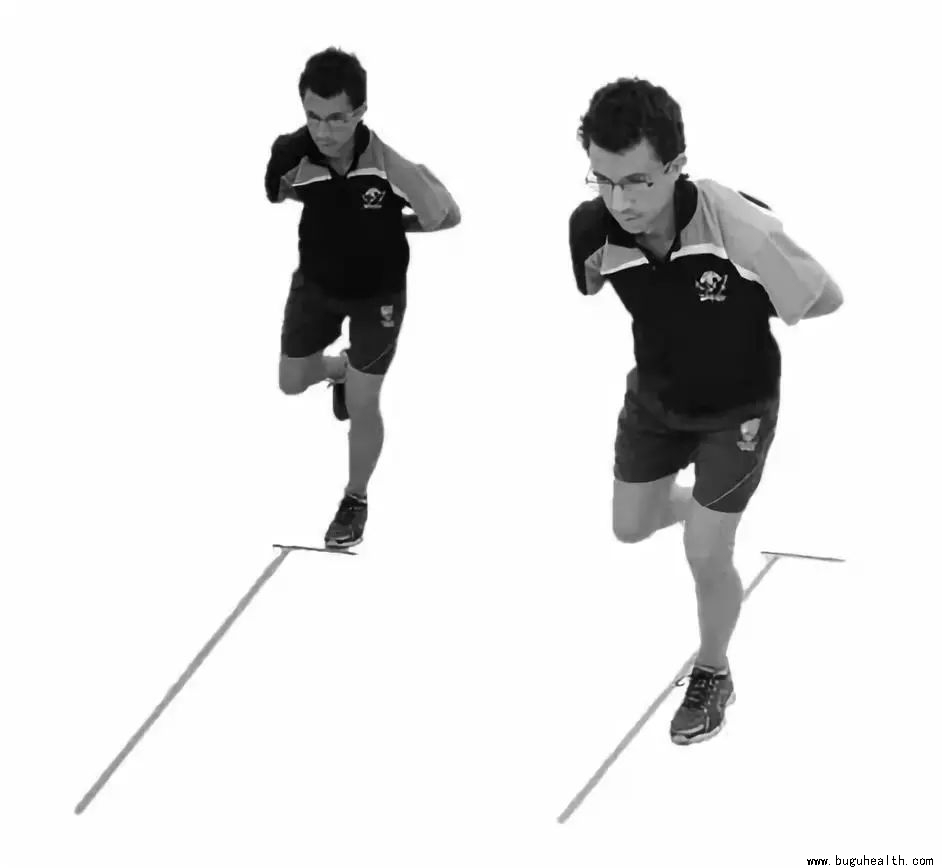

- 落地错误评分系统(Landing Error Scoring System,LESS)是通过评估被评估者落地-起跳时的生物力学特征来鉴别其发生非接触性膝关节损伤(大部分ACL损伤均为非接触损伤)风险大小的临床筛查工具,其评估结果具有较高的可信度。.....

- 布骨医学科普:什么时候可以安全的跑步(前叉重建术后) 布骨康复医疗中心 ,2022-03-09

- 做完前交叉韧带重建手术之后,能够跑步是一件大事。从术后康复的整体过程来看,尤其是对于运动人群来说,这是一个非常重要的里程碑。不过,很遗憾的是,很多人在开始恢复跑步的时候,他的身体和膝关节并没有达到应该达到的“标准”。.....